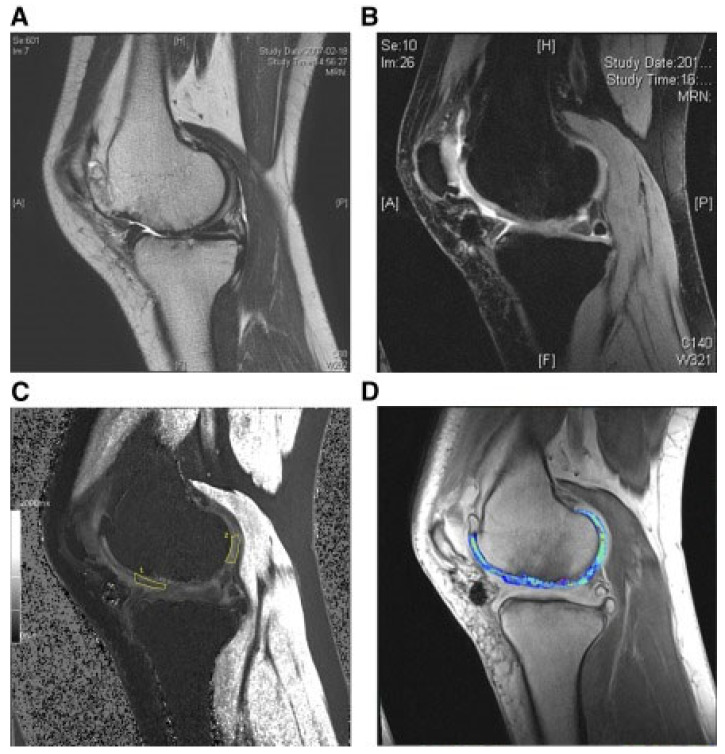

還評(píng)估了人臍帶血來(lái)源的間充質(zhì)干細(xì)胞(HUCB-MSC)治療軟骨再生的安全性和有效性。根據(jù)國(guó)際軟骨修復(fù)協(xié)會(huì)的數(shù)據(jù),HUCB-MSC用于治療7名患有KLIII級(jí)OA和IV級(jí)軟骨缺損的患者。同種異體HUCB-MSC在體外生長(zhǎng),然后與HA水凝膠結(jié)合并應(yīng)用于損傷部位。微骨折方案與這些細(xì)胞結(jié)合使用。12周后,修復(fù)的組織似乎成熟,24周后,臨床評(píng)分增加。在整個(gè)7年隨訪過(guò)程中,臨床改善的穩(wěn)定性也值得注意。組織學(xué)用于在手術(shù)后一年顯示透明軟骨,而MRI用于在手術(shù)后3年顯示軟骨再生,如圖所示圖3(其中釓-DTPA用作造影劑,以藍(lán)色顯示)。

(A) 術(shù)前軟骨缺損。(B) 移植后3年軟骨再生。(C) 通過(guò)在標(biāo)記區(qū)域采樣來(lái)計(jì)算相對(duì)軟骨松弛率的變化。(D) 顯示與藍(lán)色信號(hào)相關(guān)的GAG含量增加。